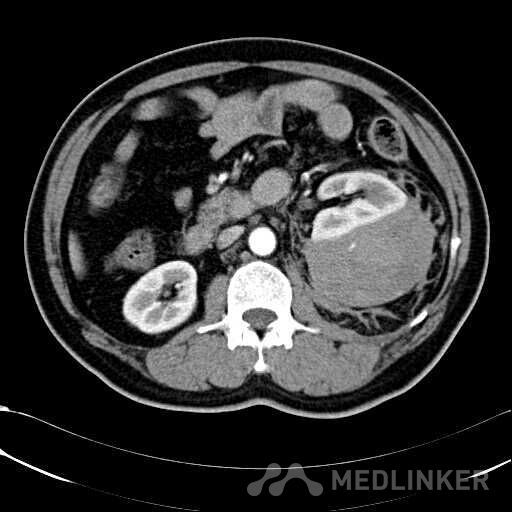

患者是54岁男性 主 诉: 突发左腰部疼痛3小时。 现病史: 缘于入院前3小时患者无明显诱因出现左腰部剧烈疼痛,无向他处放射,与活动及体位无明显关系,伴有腹胀、恶心、呕吐,无头痛、头晕,无人事不省、口吐白沫,无胸闷、胸痛、咯血,无发热、畏冷、寒战,大小便未解,肛门无停止排气,遂就诊我院,查“泌尿系彩超:左肾实质及不均质回声区,范围约9.4*4.1cm,界不清,内未见明显血流信号”,为进一步治疗,门诊拟“左肾占位”收住入院,发病以来,患者精神欠佳,未进食,大小便如前述,体重无明显改变。 患有“高血压病”7年,规则服药治疗(具体不详),监测血压情况不详。 T: 36.5 ℃ P: 65 次/分 R: 20 次/分 BP: 154/94 mmHg 双肾区皮肤无红肿、破溃及隆起,双肾肋下均不能被触及,左侧肾区叩击痛明显,右侧肾区无叩击痛,双侧肾区未闻及血管杂音。膀胱区无隆起,无压痛,耻骨上膀胱区叩诊空虚。外生殖器发育正常。 2016-04-12 泌尿系彩超:左肾实质及不均质回声区,范围约9.4*4.1cm,界不清,内未见明显血流信号。 04-12血常规:血红蛋白 151 g/L,白细胞 16.80 10^9/L,中性粒细胞百分比 84.90 %。急诊生化:白蛋白 39.8 g/L,葡萄糖 9.46 mmol/L。